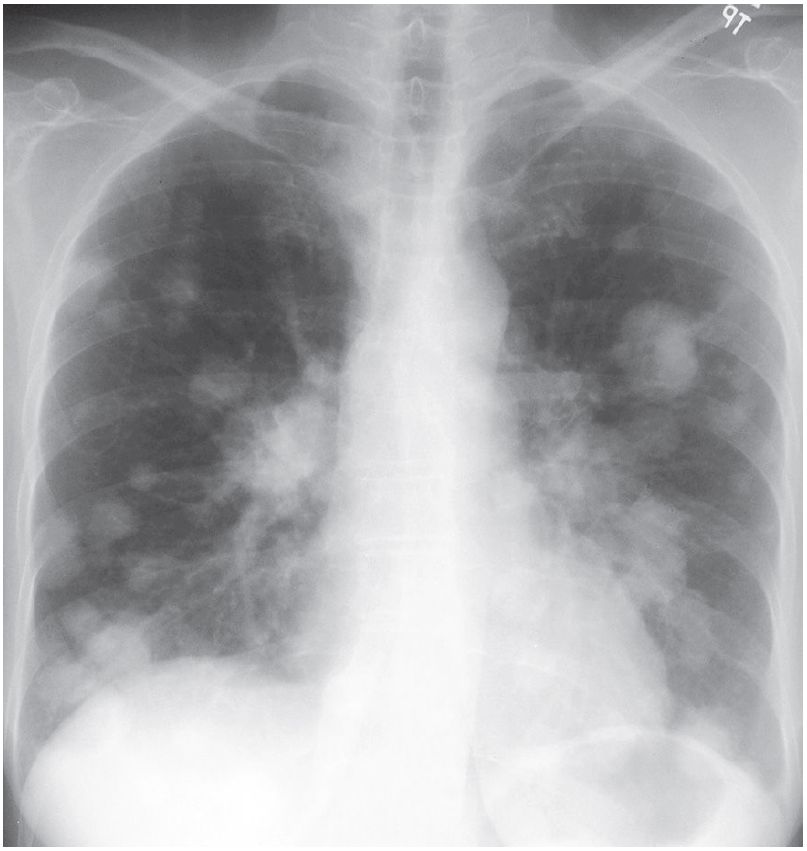

Post Hysterectomy for Uterine Cancer Post category:Spot Diagnosis Post published:May 24, 2023 Share on Facebook Share on X (Twitter) Share on Pinterest Share on Email Share on Reddit 50-year-old woman status post hysterectomy for uterine cancer 50-year-old woman status post hysterectomy for uterine cancer. What’s the Diagnosis ? FULL CASE AND ANSWER Share on Facebook Share on X (Twitter) Share on Pinterest Share on Email Share on Reddit Read more articles Previous PostAcute Flank Pain and Nail Changes Next PostPtosis and Anisocoria after Traumatic Head Injury You Might Also Like Patient with Acute Dyspnea and Chest Pain and a History of Peptic Ulcer April 10, 2022 Phlegmasia Cerulea Dolens (Deep Vein Thrombosis) May 10, 2021 A 20-year-old man with Increasingly Frequent Bloody Diarrhea and Weight Loss January 13, 2022